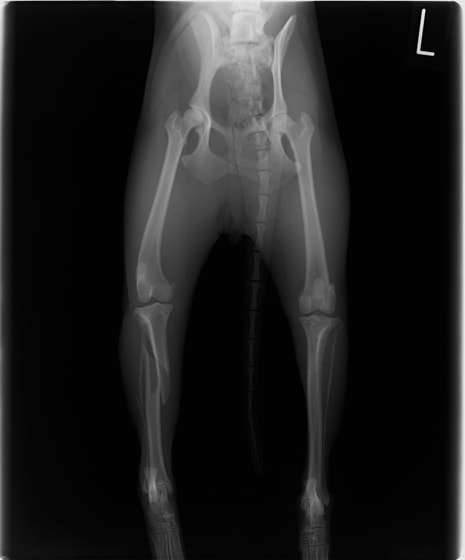

症例3:キルシュナーワイヤーのピンニングによる整復

ペルシャ猫 11ヶ月齢 雄

他院にて左大腿骨遠位の成長板骨折(salter-harrisⅠ型)が認められており、治療相談を目的として来院。当院にて、キルシュナーワイヤーを用いたピンニングにより骨折部位の整復を行いました。術後の経過は良好で、現在も経過観察中です。

術前レントゲン

術後レントゲン